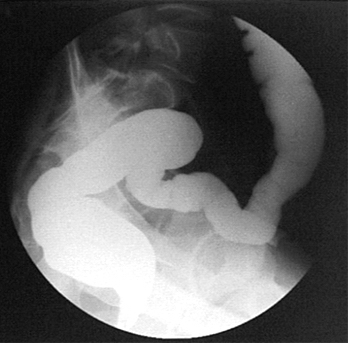

Ирригоскопия (рентген)

Ирригоскопия прямой и сигмовидной кишки при тугом наполнении контрастным веществом.